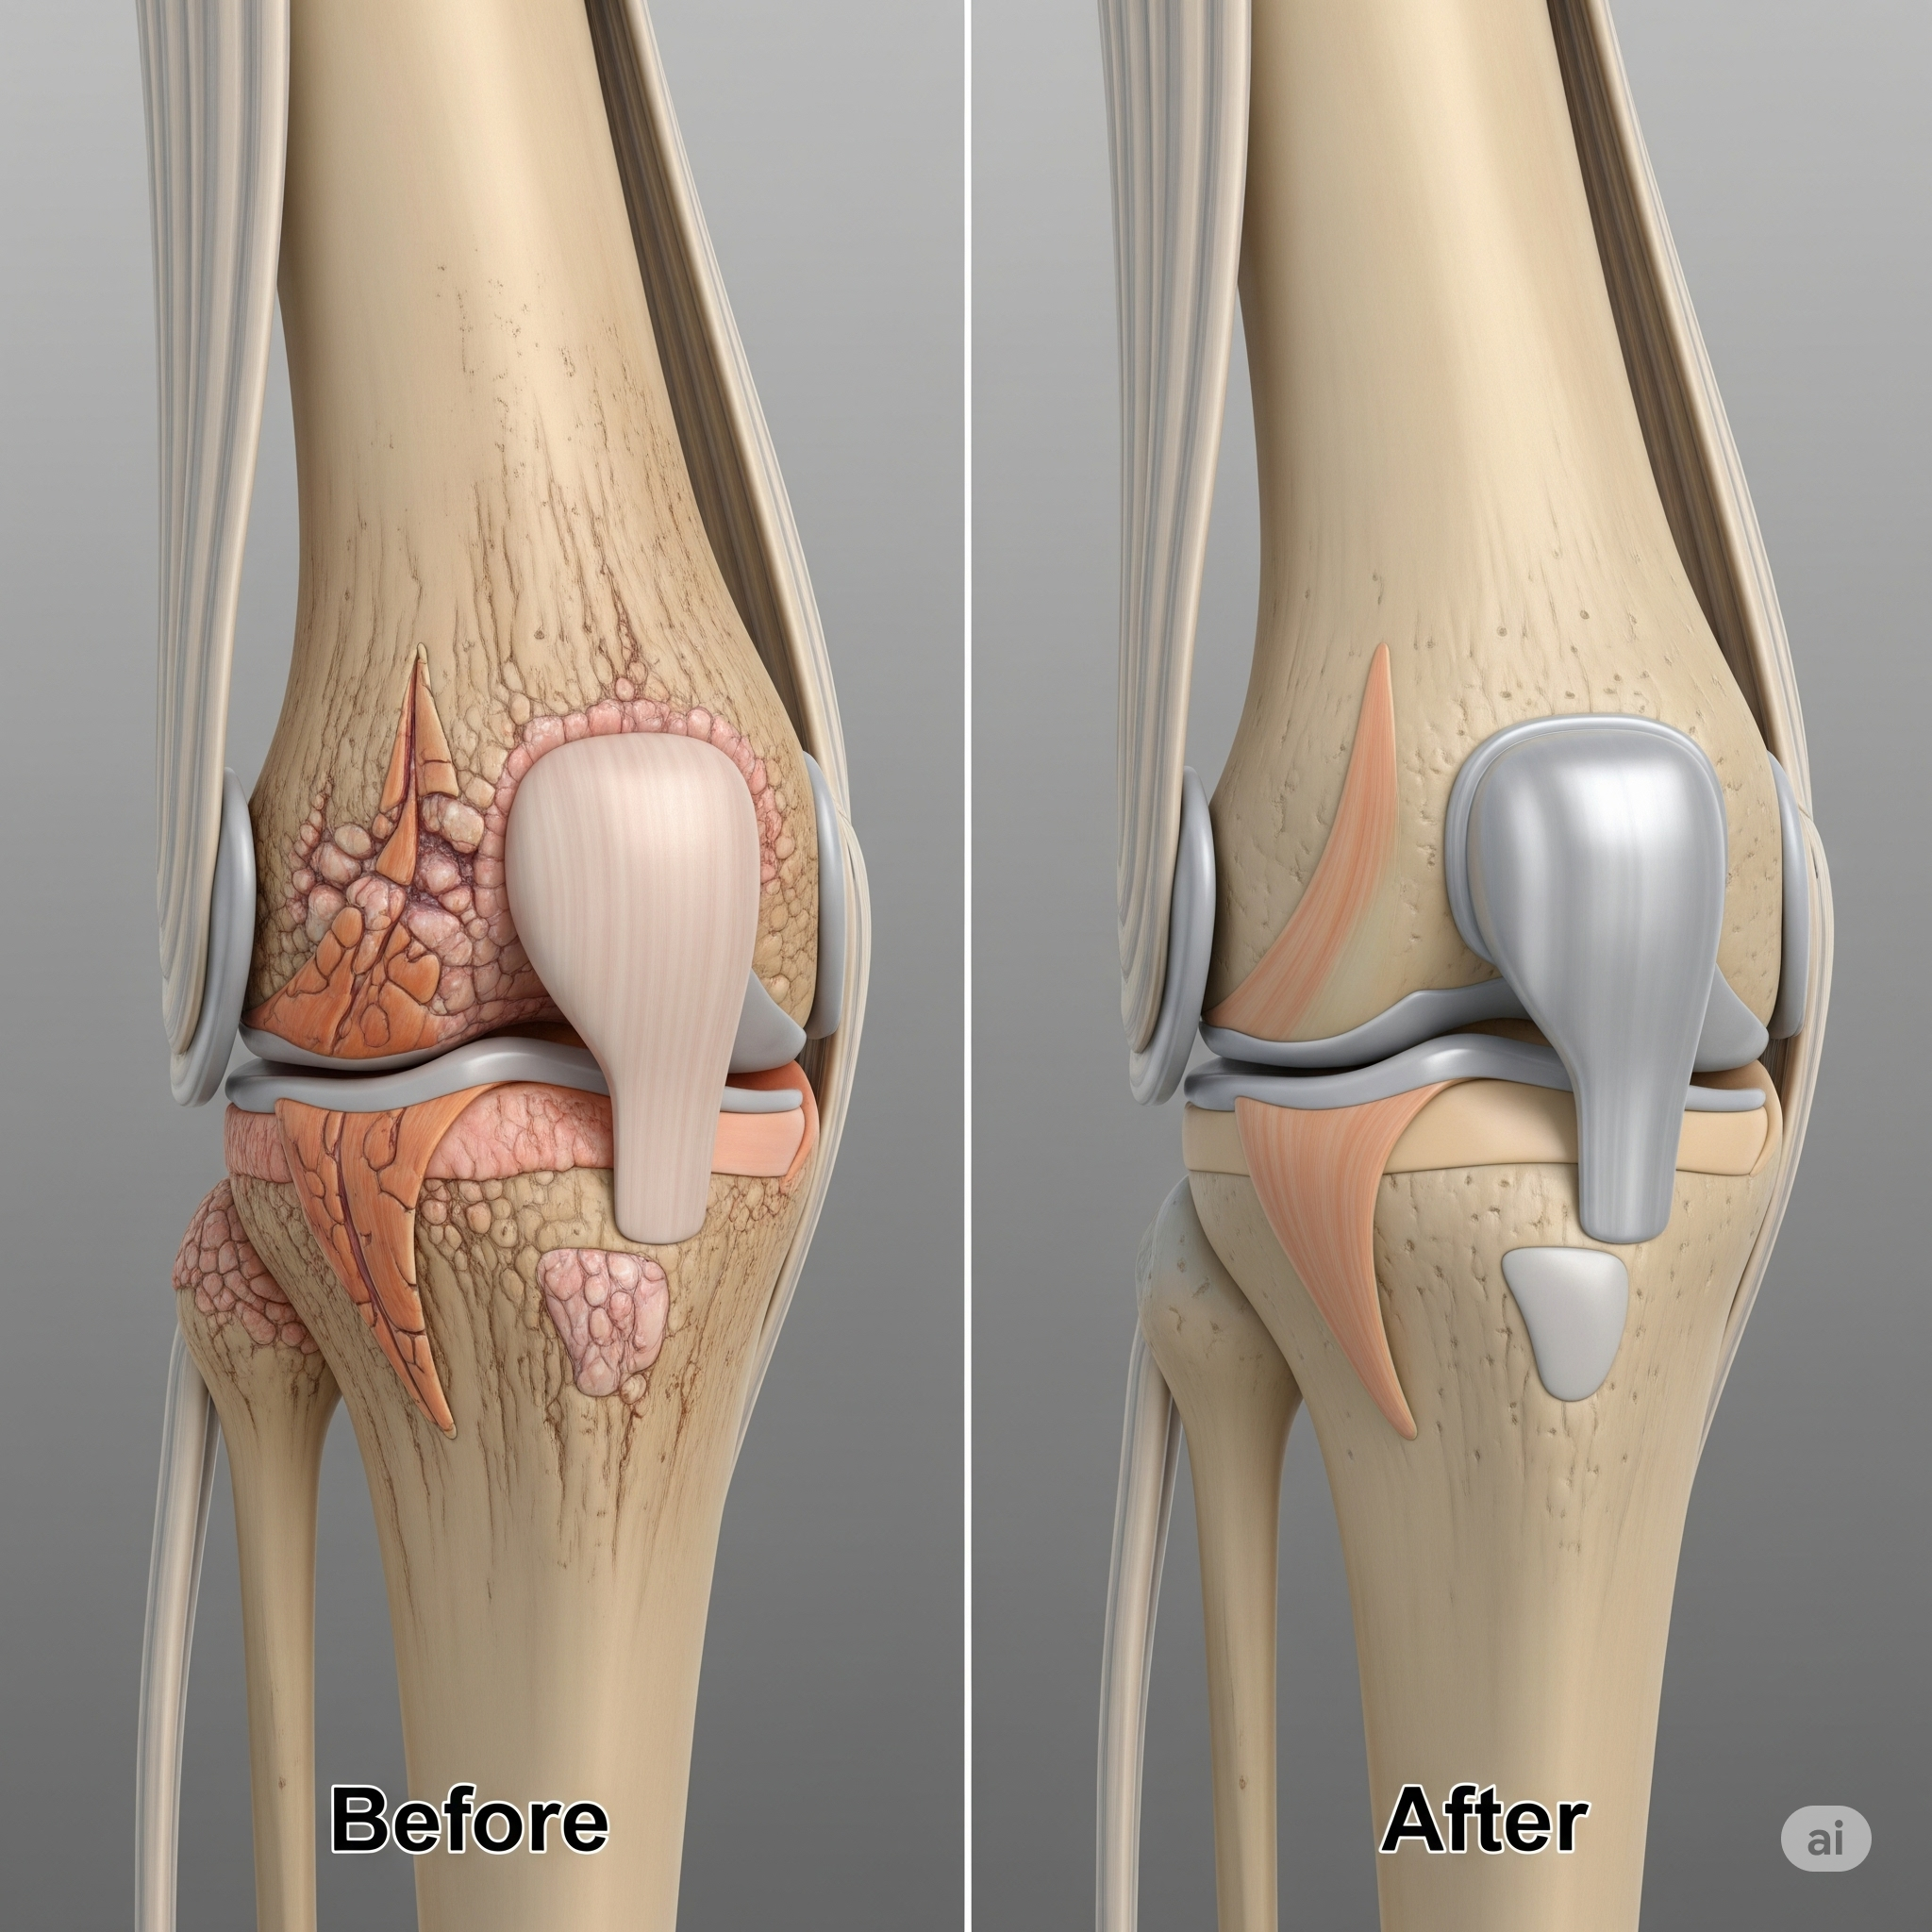

Knee replacement surgery, also known as knee arthroplasty, is a highly effective procedure to relieve severe knee pain and restore function in a damaged knee joint. This surgery is often recommended for individuals suffering from conditions like osteoarthritis, rheumatoid arthritis, or post-traumatic arthritis, where conservative treatments are no longer providing relief. The procedure involves replacing the damaged cartilage and bone of the knee joint with artificial components made of metal and plastic. This comprehensive guide will walk you through everything you need to know about knee replacement, from the signs you might need it to the recovery process.

- Total Knee Replacement (TKR): This is the most common type. It involves replacing the entire joint—the lower end of the thigh bone (femur), the upper end of the shin bone (tibia), and often the kneecap (patella)—with artificial components.

Knee replacement surgery typically takes 1 to 2 hours. You will receive either general anesthesia (you are asleep) or a spinal anesthetic (you are awake but numb from the waist down). The surgeon makes an incision at the front of the knee to access the joint. The damaged bone and cartilage are carefully removed, and the new metal and plastic components are precisely fitted and cemented into place. Once the implants are secured, the surgeon closes the incision.